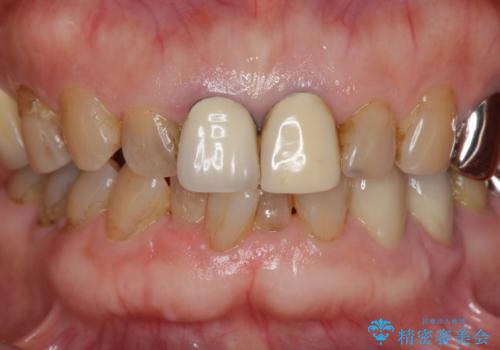

前歯の審美改善

- 孫娘の結婚式に合わせて前歯を綺麗にして写真映りをよくしたいと来院されました。

結婚式に合わせて根管治療からのやりかえを短期集中治療で計4回で終える計画を立てます。

- 40万円(仮歯・ファイバーコア・ジルコニアクラウン×3)費用は治療当時の料金となります

セラミック治療は外から見えるのはクラウンの色味・形態、歯肉の状態のみですが、X線撮影において現れるクラウンと歯牙の適合や、ファイバーコアの精度・根管充填の密度に、より長い予後を達成するための要素が含まれると考えます。